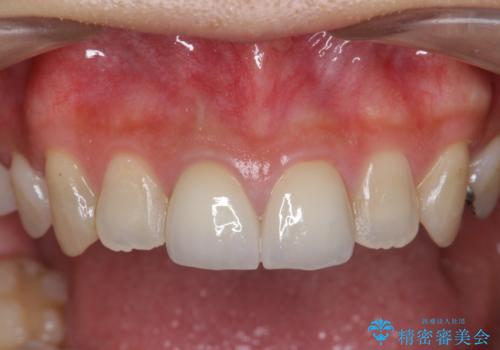

前歯 審美改善セラミック治療

ジルコニアクラウンによる審美性の改善を計画します。

神経をとる治療を行った歯は、時間が経過すると術前のように変色し見た目を大きく損ないます。

このような場合金属を使わないジルコニアクラウンを用いた治療を行うことで天然の歯のように審美性を改善することが可能になります。